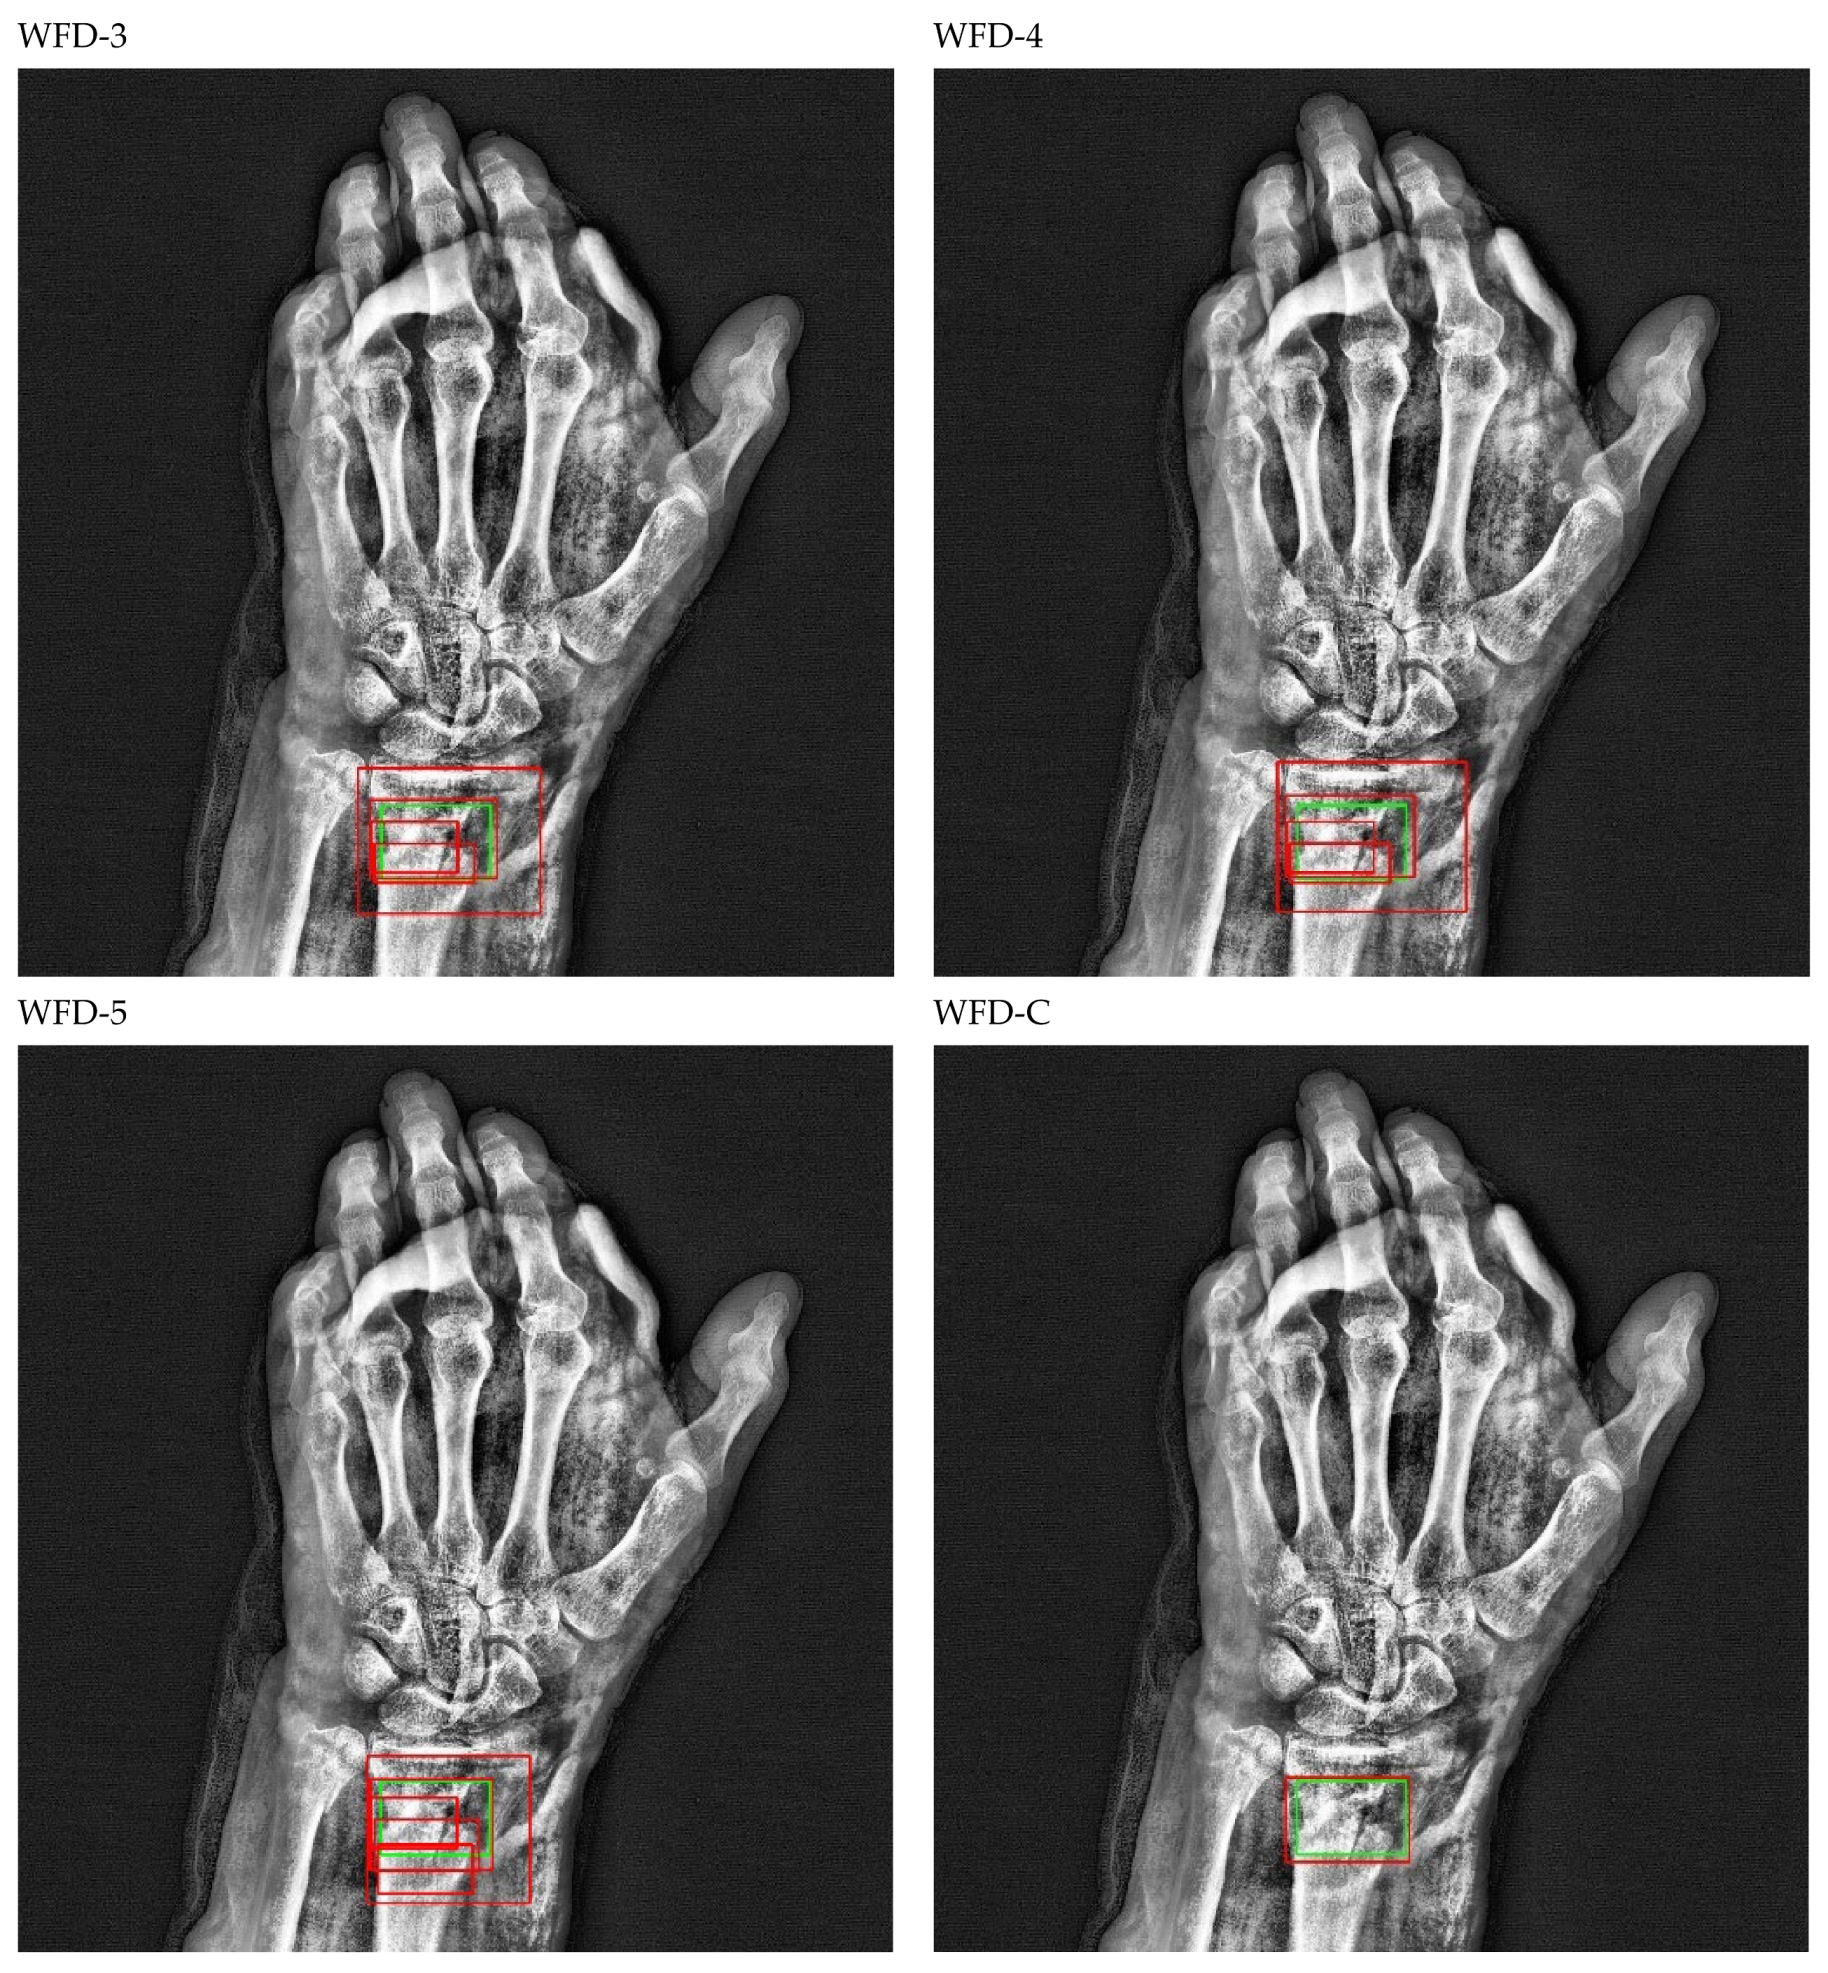

The bounding box outputs achieved from fracture detection performed with ensemble models in wrist X-ray images are provided in Figure 20 and Figure 21 below as a sample for the right/left hand in the dataset.

Figure 20.

Sample of right wrist fracture results [ground-truth bounding box (green), predicted bounding box (red)].

Figure 21.

Sample of left wrist fracture results [ground-truth bounding box (green), predicted bounding box (red)].

The predicted bounding boxes achieved fracture detection suggest that, as shown in the images in Figure 20 and Figure 21, the model that provides the most accurate results that are closest to the ground-truth bounding boxes is the WFD-C ensemble model developed in this study. Moreover, the examination of the number of predicted bounding boxes reveal that the model with the lowest number on the test data is also WFD-C. For the fracture detection in wrist X-ray images, Figure 22 below shows the total number of predicted bounding boxes obtained for each model on the test dataset as the result of the fracture detection performed with a total of 26 deep learning models, six of which are ensemble models.